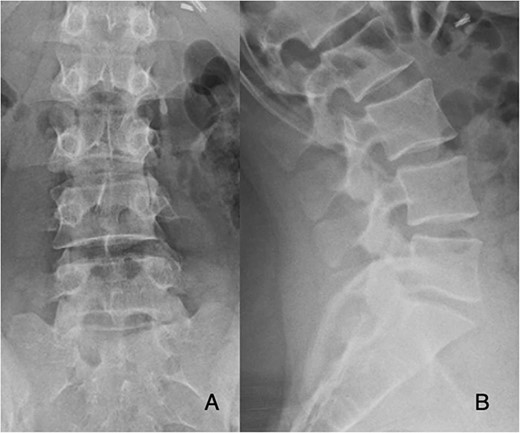

Preoperatively, her physical exam demonstrated left-sided quadriceps weakness and minimally diminished sensation in an L3-L5 distribution. The patient’s magnetic resonance imaging (MRI) demonstrated degeneration of the L5-S1 disc with disc height loss and left-sided L5-S1 foraminal stenosis (Figs 1 and 2).

T2-weighted MRI sagittal and axial cuts demonstrate recurrent disc herniation with left-sided foraminal stenosis and degenerative changes at L5-S1.